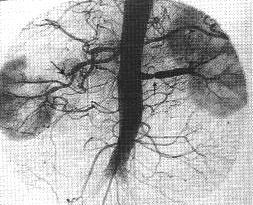

多发性大动脉炎(造影)

多发性大动脉炎。动脉期示左右肾动脉近端1/3有一向心性管状狭窄,狭窄后肾动脉稍扩张,腹主动脉亦见长段的狭窄。

多发性大动脉炎:狭窄多位于肾动脉起始段,狭窄段光滑呈管状,常伴有狭窄后扩张,腹主动脉、骼总动脉或胸主动脉同时有狭窄与扩张相间,甚至动脉瘤扩张表现。